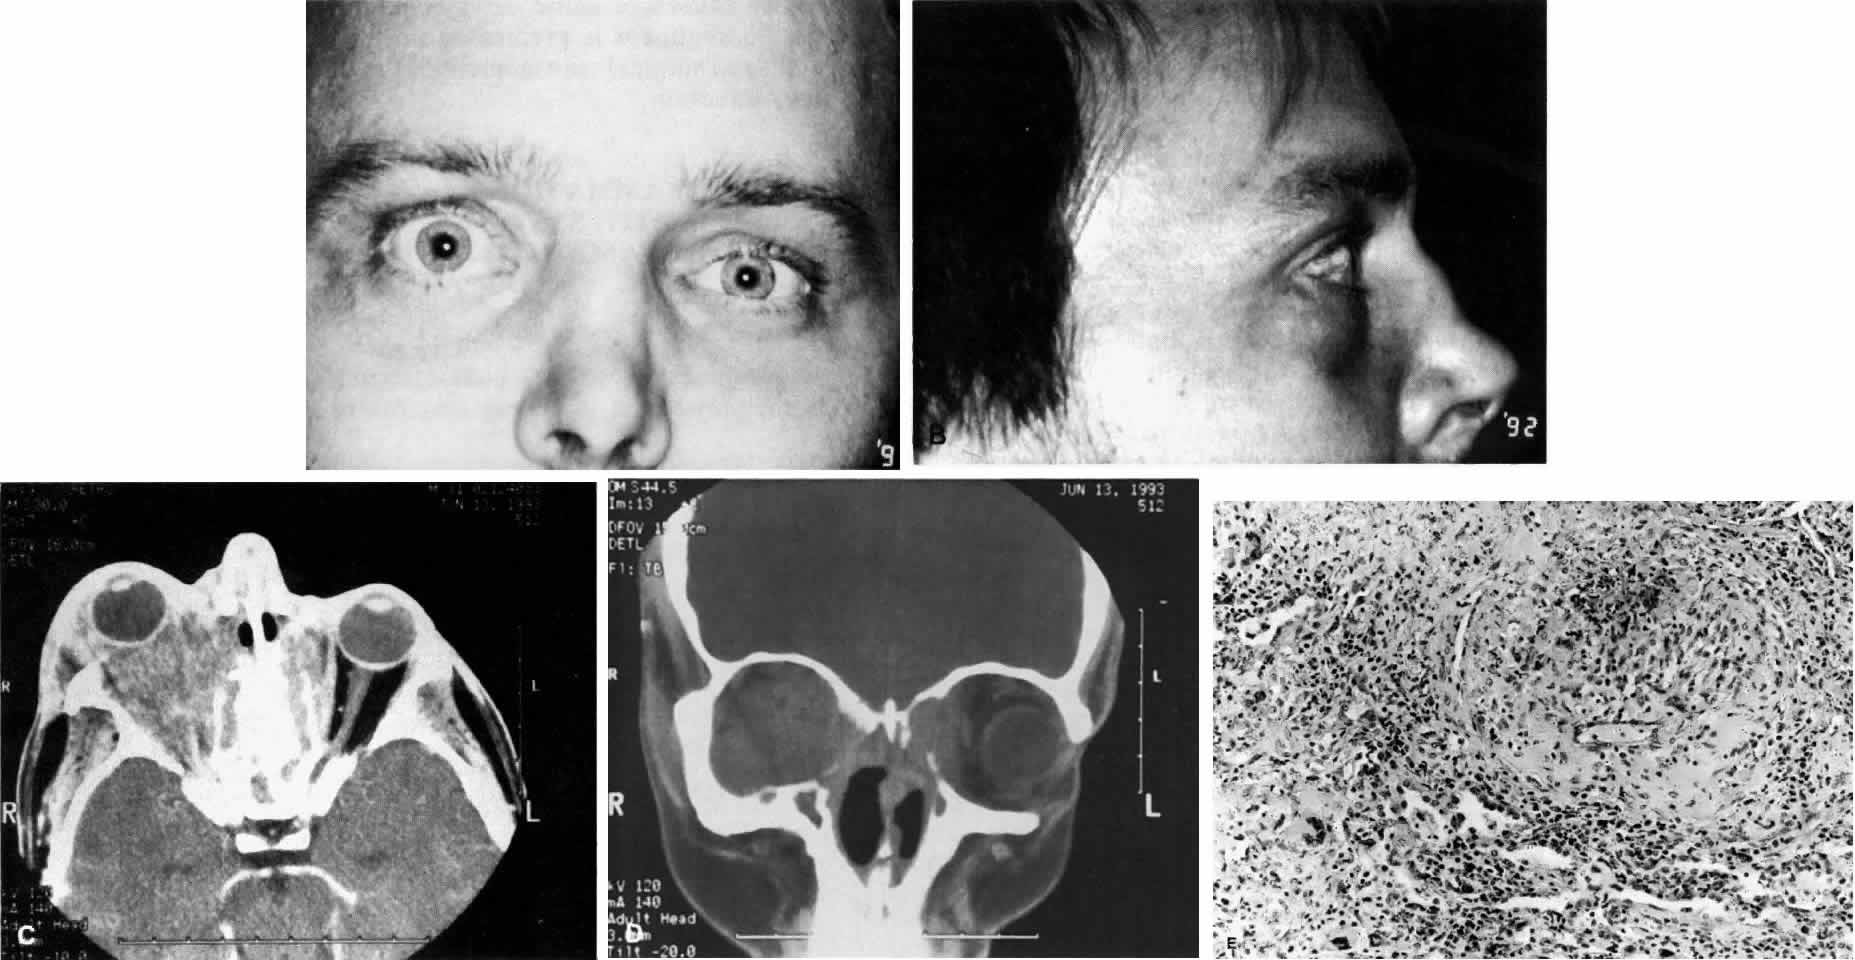

Wegener's granulomatosis is characterized by inflammatory lesions of the upper respiratory tract, lower respiratory tract, the kidneys, and, to varying degrees, generalized small vasculitis of other structures, including the eye (Figs. 10 AND 11). The definitive diagnosis is confirmed by biopsy. A limited form of the disease has been described that spares the kidneys.

Fig. 10. A. This 68-year-old woman presented with acute orbital inflammation, pain, and diplopia. Clinical evaluation demonstrated a medial orbital mass. Biopsy of the orbital mass demonstrated significant vasculitic and granulomatous changes believed to be consistent with Wegener's granulomatosis. No systemic disease was present. B. Appearance of same patient after treatment with prednisone and cyclophosphamide demonstrating complete resolution of the inflammatory process.

Fig. 11. A. This 31-year-old man has had Wegener's granulomatosis for 2 years. His disease process is stable on chronic corticosteroid therapy. He has no evidence of systemic disease. Note right-sided proptosis and hyperglobus. B. Profile of same patient demonstrating collapse of nasal bridge from bony destruction secondary to Wegener's granulomatosis. Note presence of swelling in lower eyelid. C. Axial CT image from the same patient demonstrating significant bilateral disease and bony destruction. Despite the extent of the orbital process on the right, the patient does not have diplopia. D. Coronal CT image showing destruction of medial orbital walls, vomer, and orbital septum. E. Pulmonary biopsy specimen from patient with orbital signs contains an almost obliterated vessel to right of center and scattered giant cells on left (H&E, ×160).

Ocular manifestations include orbital inflammation, scleritis, keratitis, and uveitis. The ocular involvement can occur from extension of sinus and nasal lesions or from focal small vessel vasculitis.